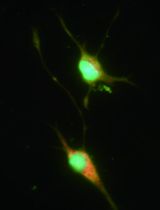

27. α-SMA antibody for immunofluorescence analysis (1:100) (Abcam, catalog number: ab5694)

10. Confocal microscope (Leica Microsystems, model: TCS SP8)